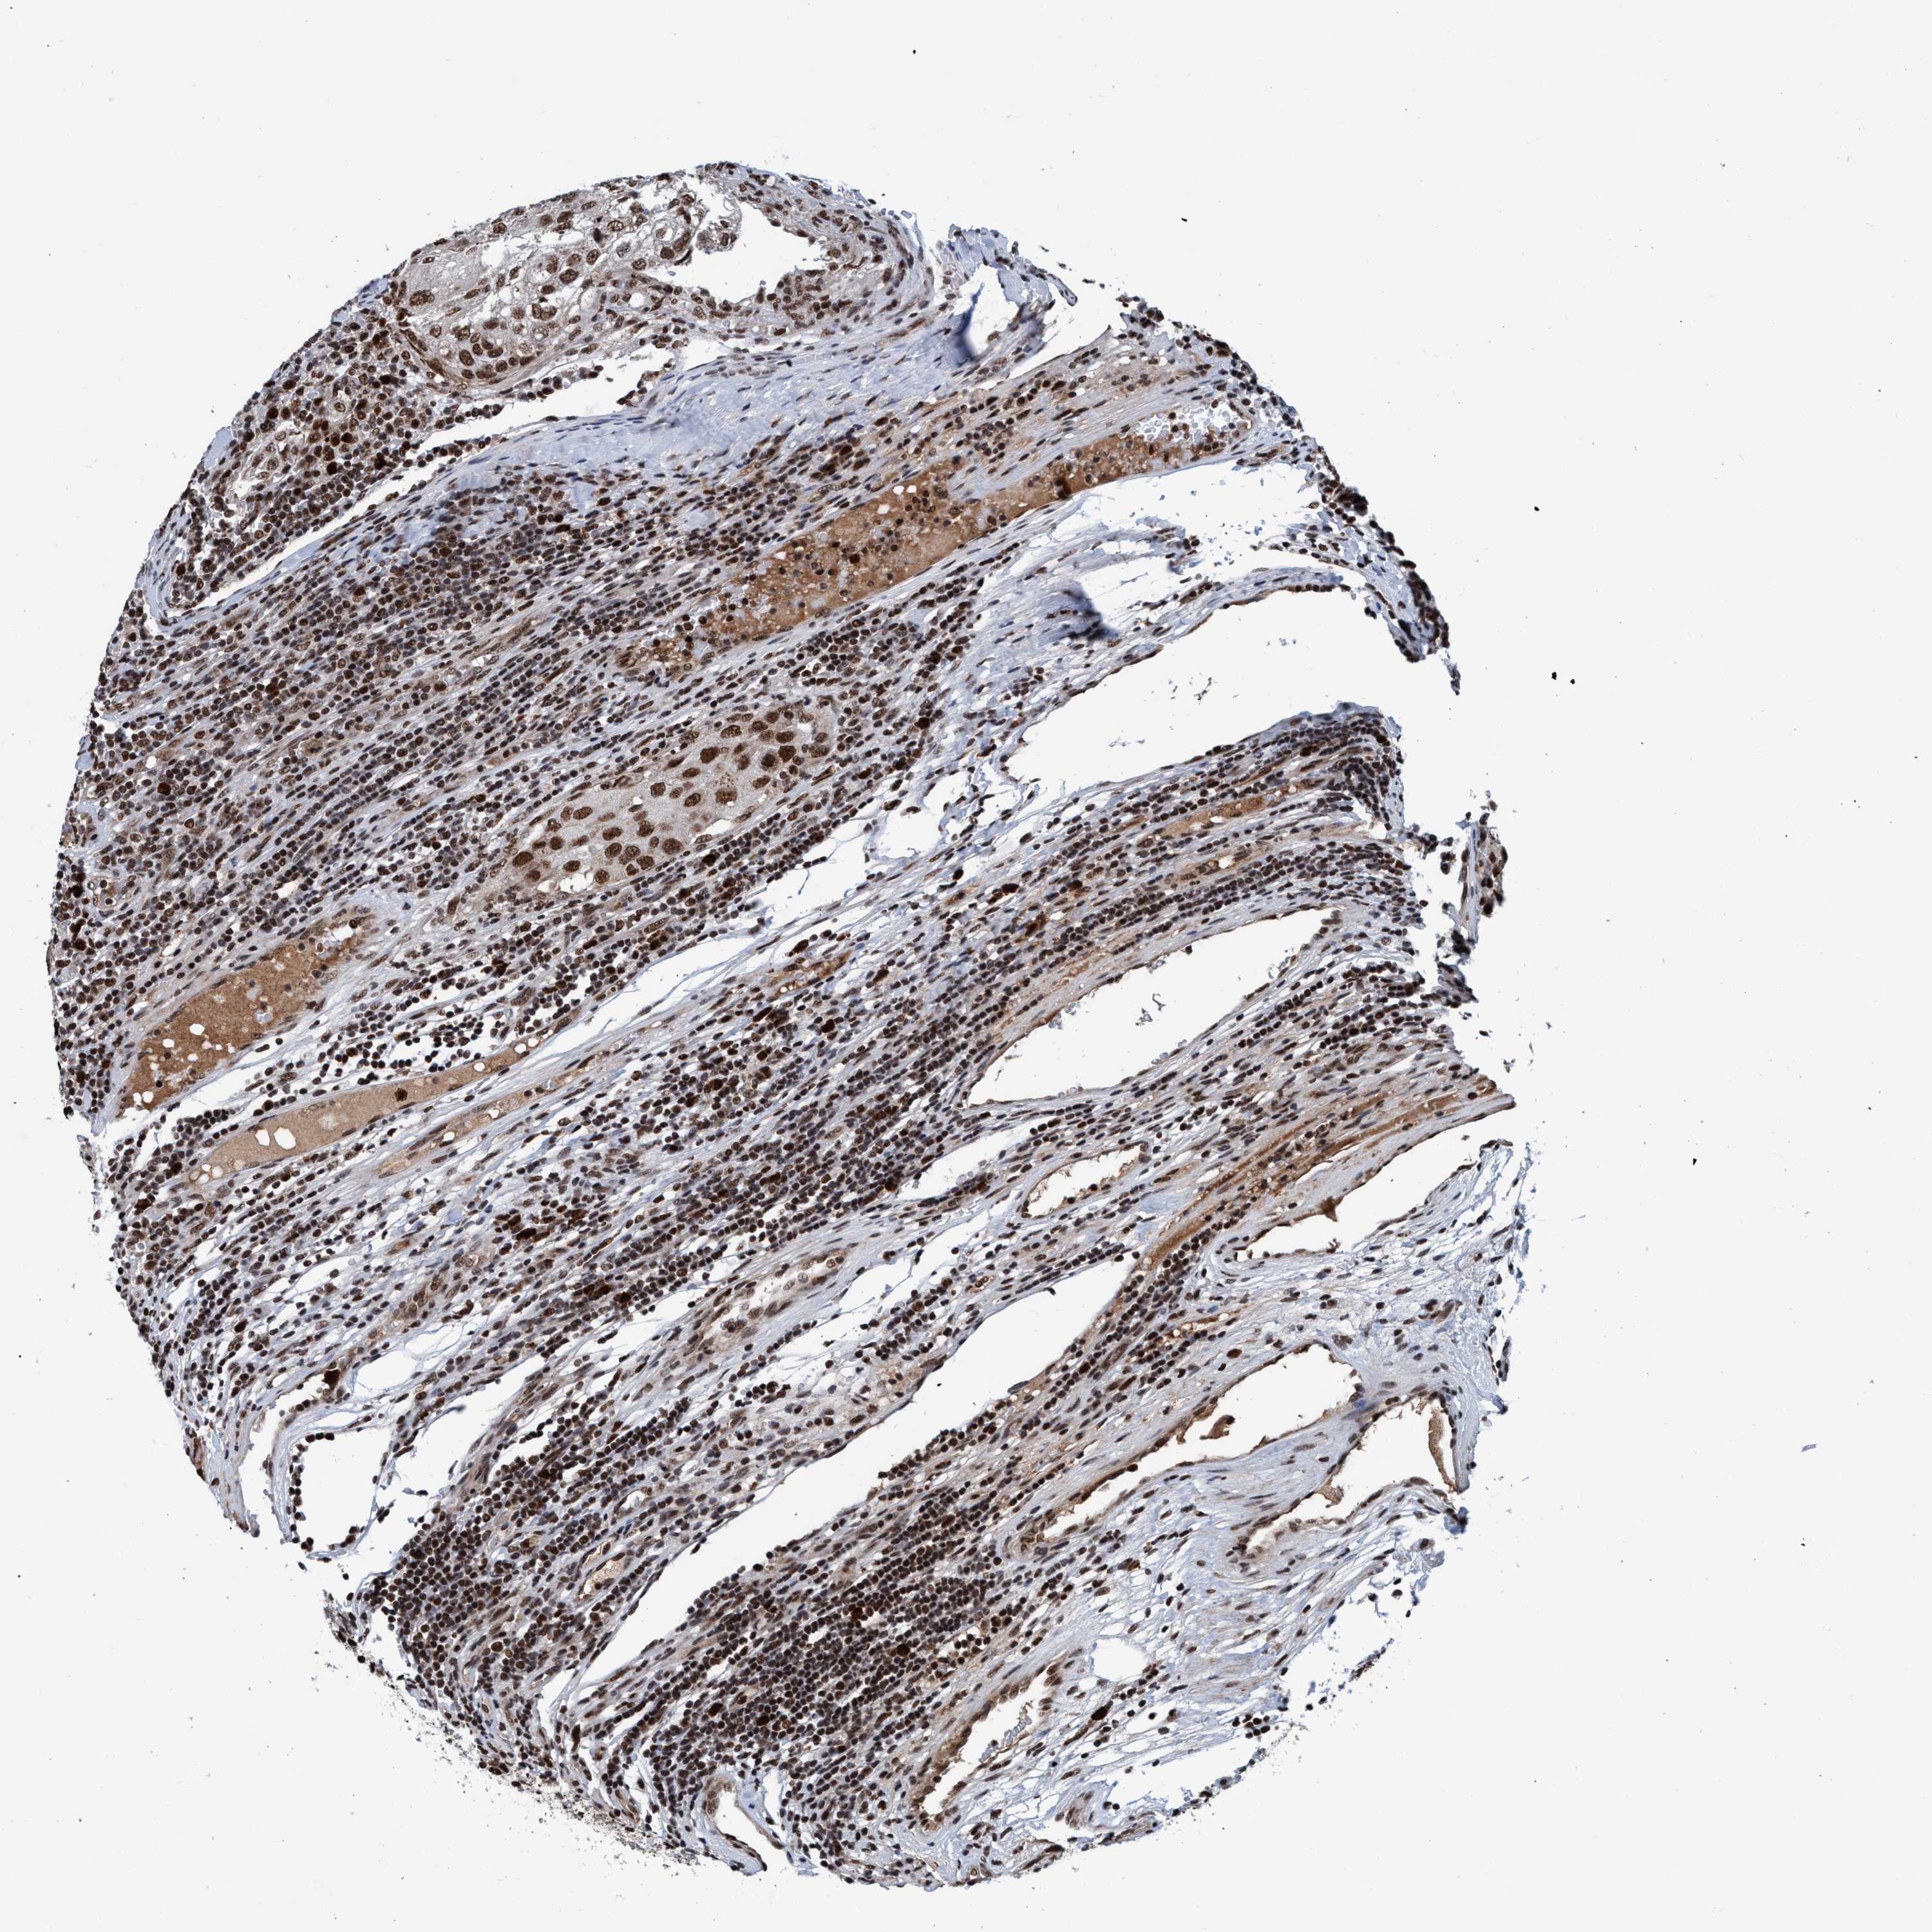

UROTHELIAL CANCER - Protein expressioni

A mouse-over function shows sample information and annotation data. Click on an image to view it in a full screen mode. Samples can be filtered based on level of antibody staining by selecting one or several of the following categories: high, medium, low and not detected. The assay and annotation is described here.

Note that samples used for immunohistochemistry by the Human Protein Atlas do not correspond to samples in the TCGA dataset.

Antibody stainingi

Antibody staining in the annotated cell types in the current human tissue is reported as not detected, low, medium, or high, based on conventional immunohistochemistry profiling in selected tissues. This score is based on the combination of the staining intensity and fraction of stained cells.

Each image is clickable and will lead to virtual microscopy that enables deeper exploration of all samples and also displays staining intensity scores, fraction scores and subcellular localization as well as patient and tissue information for each sample.

Antibody CAB022451

Staining

High

Medium

Low

Not detected

Intensity

Strong

Moderate

Weak

Negative

Quantity

>75%

75%-25%

<25%

None

Location

Nuclear

Cytoplasmic/membranous

Cytoplasmic/membranous,nuclear

Urothelial carcinoma, High grade

Urothelial carcinoma, Low grade